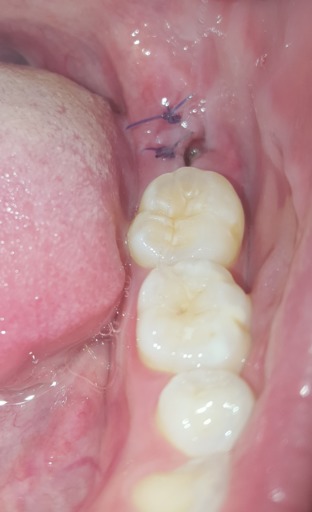

Wisdom tooth extraction - is this normal? (dry socket)

I had my wisdom tooth extracted 6 days ago and stitched up. 3 days ago, I noticed a very large hole in the gum where the site of extraction was. So far, I have not experienced any pain, soreness or tenderness. When shining a light on it, there is some yellow-ish stuff at the bottom of the socket. I have been doing warm salt water rinses to keep it clean. I wanted to know if this is normal or if it could be dry socket/infected. I also wanted to know if there was anything else I could do to help with healing.